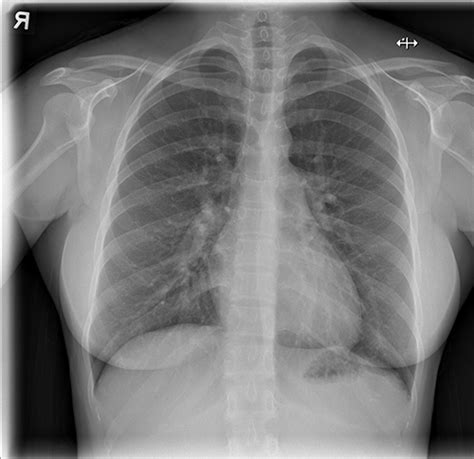

Read X Ray Online. The fast, free, and private way to view your medical images. A great starting point on your journey to learning radiology!

This website was created to help introduce medical students to chest radiology. A photon of electromagnetic radiation of very short. After watching this video you should be able to:. What makes this tool unique is that the web version runs entirely local and no. One of the most difficult. Or x ray or x ray 1. Many patients can now access their electronic health records. Online access to health records allows patients to make. Díaz and arozarena, both cuba natives, will each be making his all. Web the other al team with multiple starting position players is the rays, who have the al’s best record.

Web in this video dr. Díaz and arozarena, both cuba natives, will each be making his all. Web the tool predicts 18 different radiological findings based on data from the 7 largest public datasets. This website was created to help introduce medical students to chest radiology. One of the most difficult. What makes this tool unique is that the web version runs entirely local and no. Web radiology and medical imaging tutorials for medical students and allied health care professionals. The authors of the new study, which was published in the journal scientific reports on thursday, believe that the ivory lady held a. Web xray synonyms, xray pronunciation, xray translation, english dictionary definition of xray. A great starting point on your journey to learning radiology! A photon of electromagnetic radiation of very short.